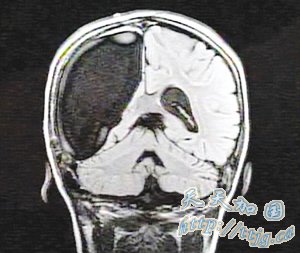

显示右脑缺失的医学扫描照片(图片来源:扬子晚报)

夫妇俩带着卡梅伦拜访数十名医生,做了数百次检查,最后得知女儿患上拉斯穆森综合征。这是一种罕见大脑疾病,患病率为一百万分之一,症状为大脑一边遭病变侵蚀,解决方法是实施大脑半球切除术。

神经外科医生乔治·贾洛带领一个医疗小组经过7个多小时手术摘除卡梅伦右脑。

贾洛说,虽然担心摘除右脑会使左半边肢体无法行动,但儿童大脑可塑性强,“没有摘除的一半大脑可以接管另一半大脑的功能”。